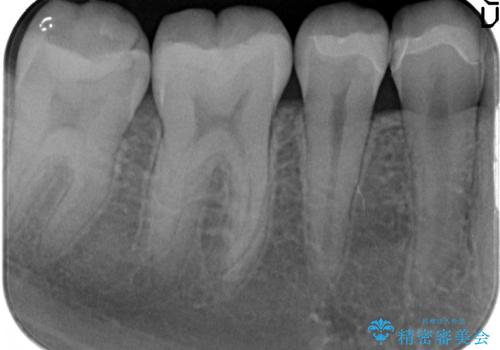

- 右下の4、5番目の歯がしみるといらっしゃった方の症例です。

右下4の遠心及び右下5の近心部が痛むとのことだったので、虫歯除去後、セラミックインレーによる修復を行いました。